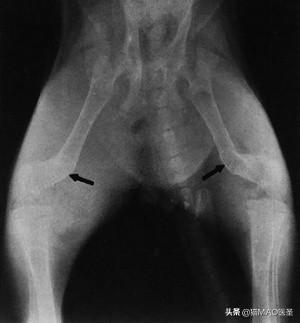

1. 严重的破骨细胞骨吸收后出现跛行,轻微的物理创伤后出现长骨骨折。椎体压缩性骨折可压迫脊髓和神经,导致运动和感觉功能障碍。

• 长腿骨和脊柱的X光片

全身骨骼受累但不均匀。在某些区域,如头骨的松质骨,病变变得更早并达到更晚期。牙槽骨吸收发生早,导致牙齿松动,容易脱落,影响咀嚼。由于上下颌骨松质骨的加速吸收,骨骼变得柔软柔韧(“橡胶颚”综合征),颌骨无法正常闭合。这经常导致流口水和舌头突出。严重脱钙的下颌骨易发生骨折和牙槽骨移位。长骨受影响较小。轻微创伤后跛行、步态僵硬和骨折可能是骨吸收增加的结果。